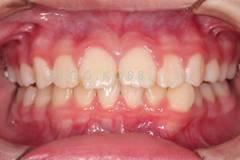

下面這個小患者就存在需早期矯正的問題。通過早期矯正,在不長的時間內(nèi)就達(dá)到極為明顯的療效。她的情況如果等到牙齒替換完畢后再解決,矯治的難度則會非常大。

早期矯正中